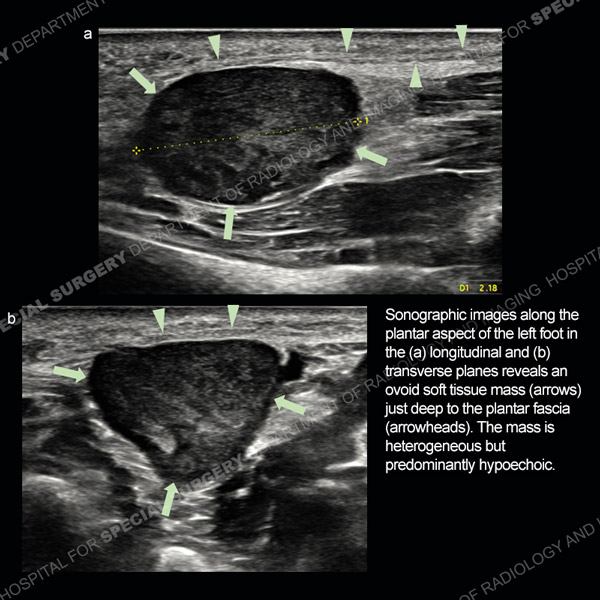

![]() |

Featured Ultrasound of the Month CaseCase 186: 64-year-old woman with new left ring finger soft tissue swelling. |